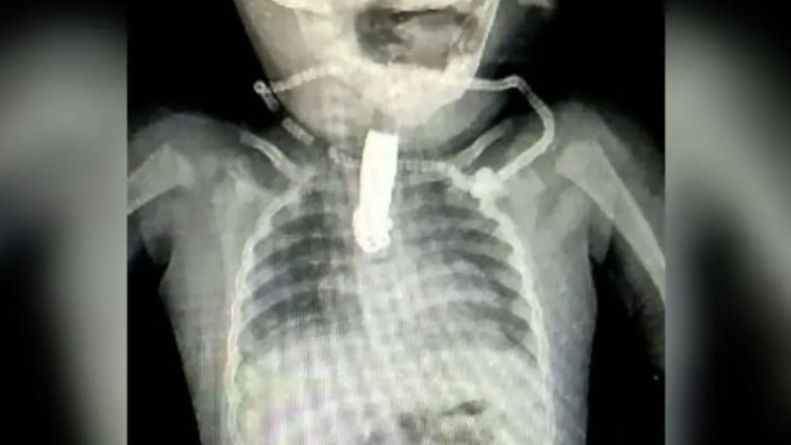

En la radiografía que le hicieron al menor se puede ver con total claridad al cortaúñas atascado en la garganta del niño. "El cortaúñas se clavó profundamente en el tracto respiratorio del bebé, lo que complica aún más el caso", comentan desde 'Times of India'. Por esa razón, el equipo médico decidió operar de urgencia al niño.